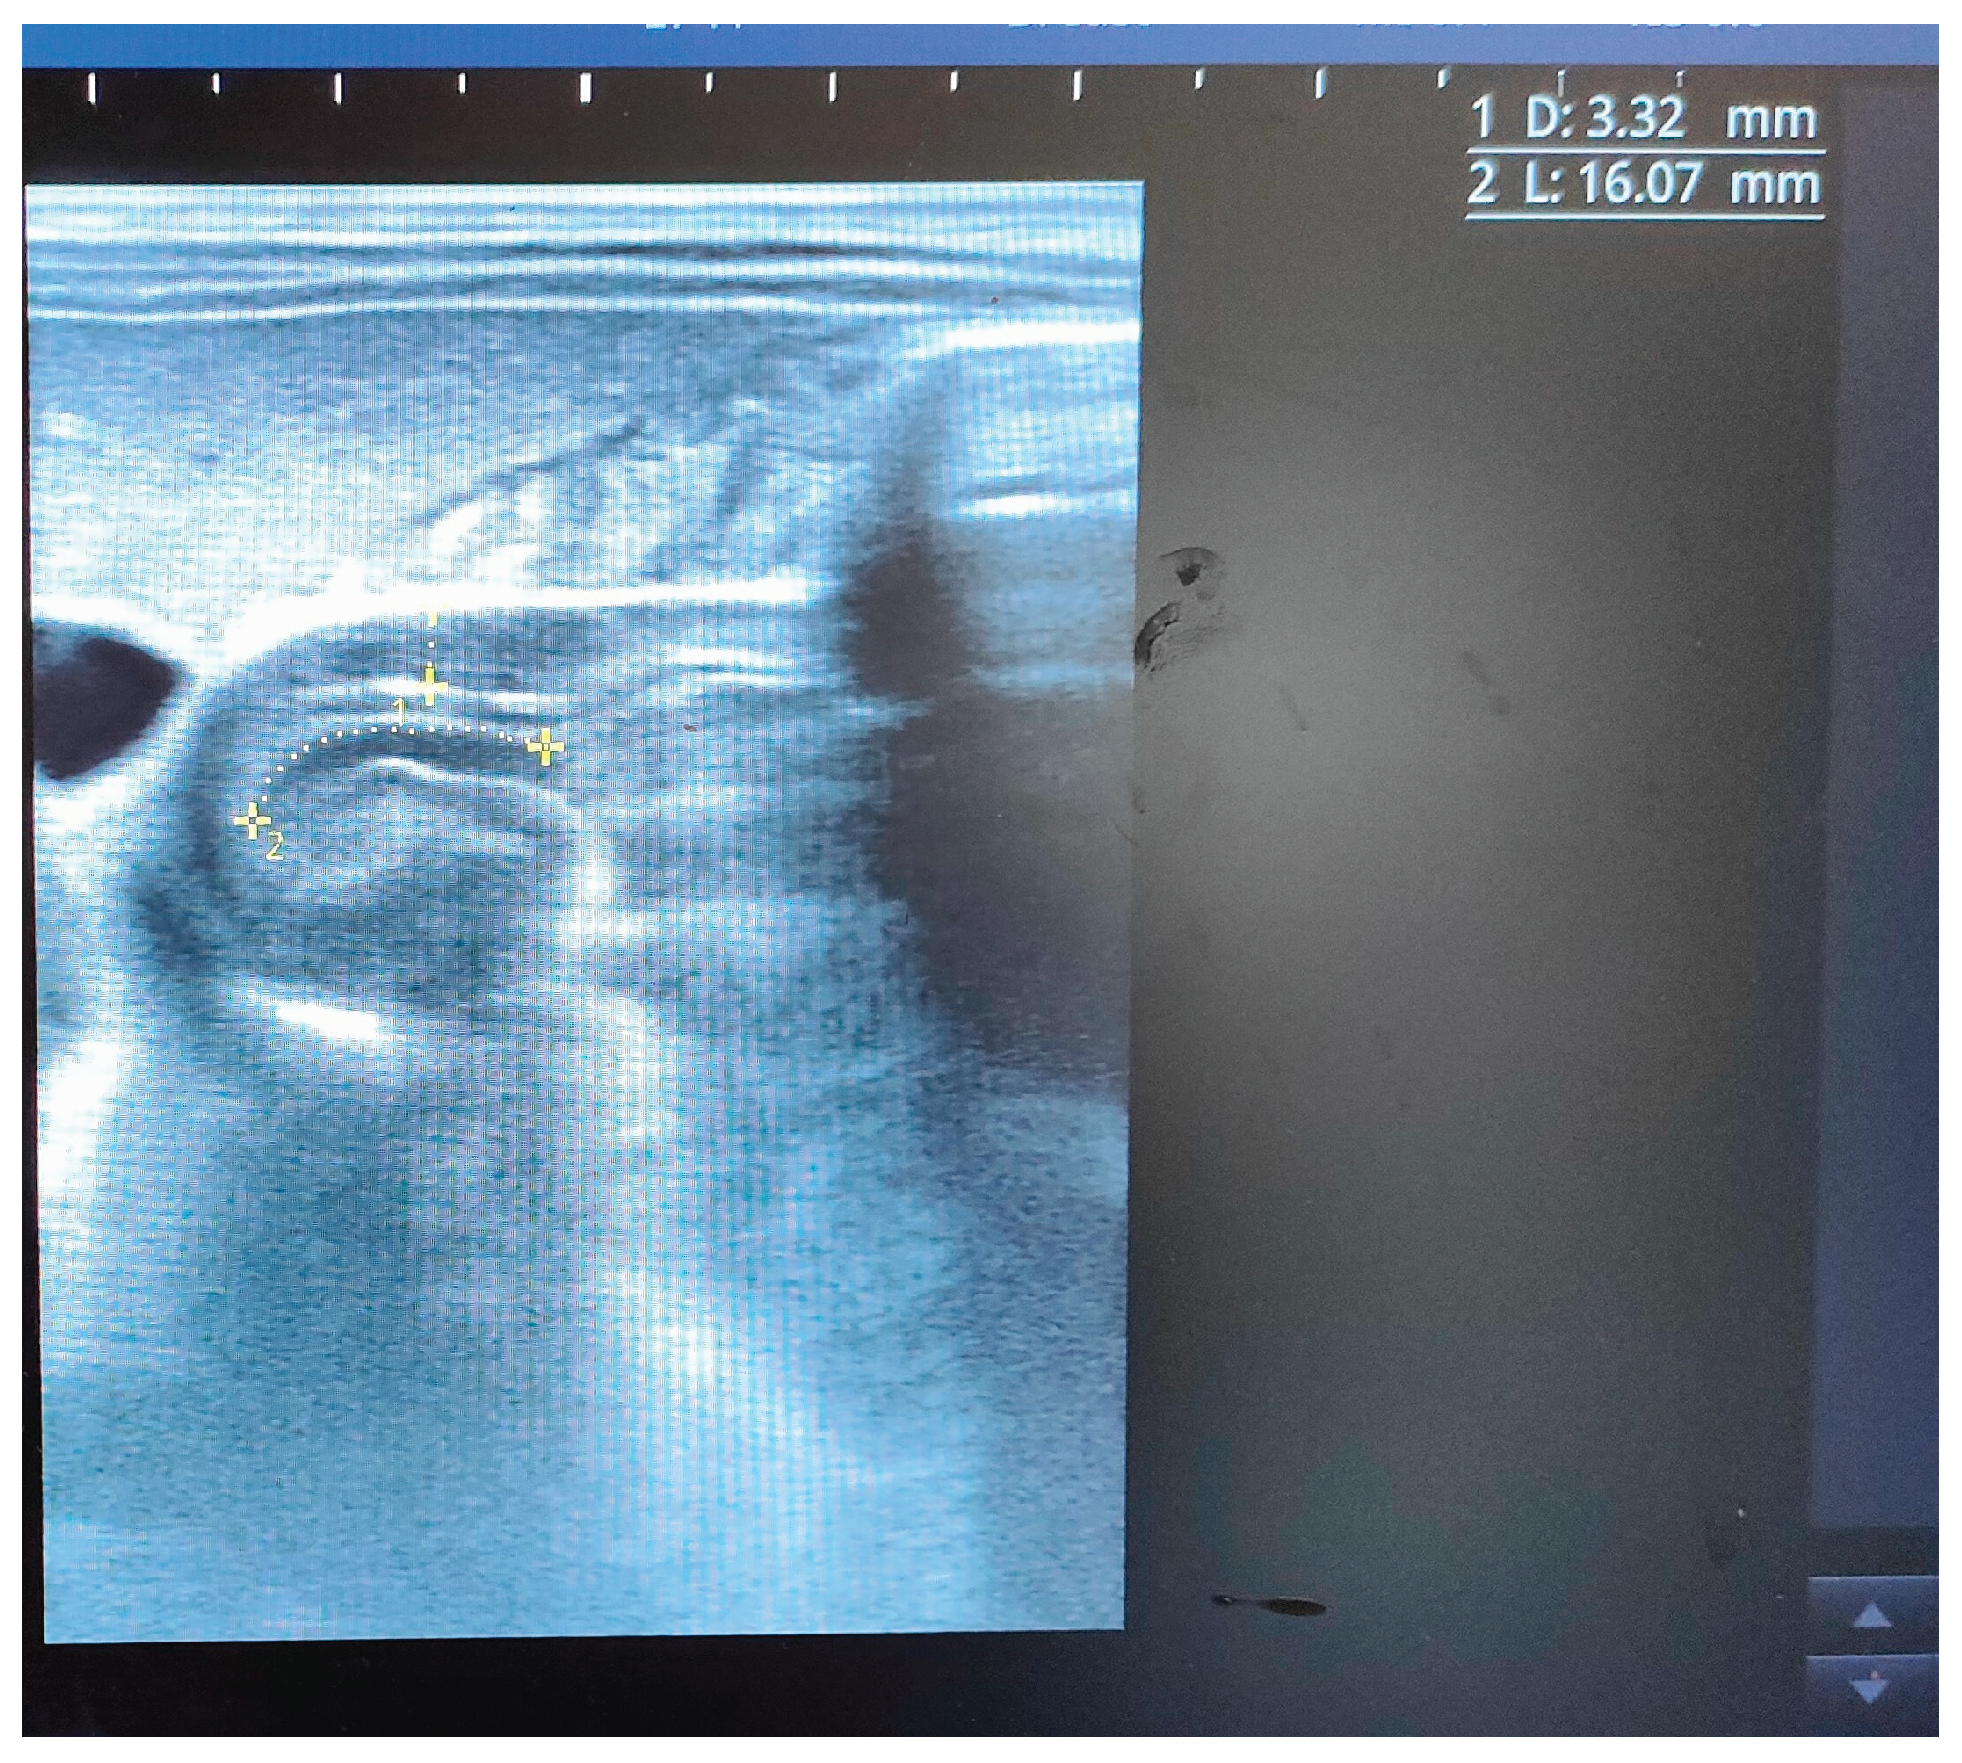

After admission, the infant presented with some projectile, non-bilious vomiting. An abdominal X-ray proved a marked gastric distension (Figure 1). An abdominal ultrasound (US) displayed a thickened pylorus with a wall thickness of 5.7 mm and a length of 17.5 mm (Figure 2). A diagnosis of hypertrophic pyloric stenosis was made.

Treatment with oral atropine, at a dosage of 0.1 mg/kg/day, administered four times per day before feeding, was started. Initially, the patient tolerated the meals and the therapy only partially, with some episodes of vomiting; some meals had to be administered several times. Sublingual ondansetron (dose 0.15 mg/kg) was administered as needed. After two weeks, meal tolerance started to improve, with a reduction of vomits and reduction ondansetron needs. The infant’s weight increased, as showned in the Figure 3. After one month, an abdominal pyloric ultrasound revealed a canal length of 16 mm and muscle thickening reduced to 3 mm (Figure 4).

Figure 2. First ultrasound image indicating pyloric hypertrophy. The image displays the initial measurement of the pyloric muscle thickness ( 5.77 mm).

Figure 4. This is a follow-up ultrasound 4 weeks after the initial evaluation. The image illustrates a decrease in the thickness of the hypertrophied pyloric muscle ( 3.32 mm vs. 5.77 mm).